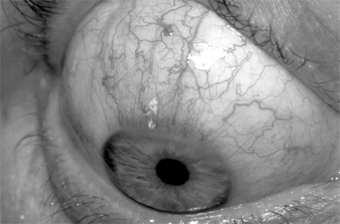

SUPERIOR LIMBIC KERATOCONJUNCTIVITIS

Superior limbic keratoconjunctivitis is usually bilateral and limited to the upper tarsus and upper limbus. The principal complaints are irritation and hyperemia. The signs are papillary hypertrophy of the upper tarsus, redness of the superior bulbar conjunctiva, thickening and keratinization of the superior limbus, epithelial keratitis, recurrent superior filaments, and superior micropannus (Figure 5-19). Rose bengal staining is a helpful diagnostic test. The keratinized epithelial cells and mucous debris pick up the stain. Scrapings from the upper limbus show keratinizing epithelial cells.

Figure 5-19

Figure 5-19: Superior limbic keratoconjunctivitis. Note the "corridor" on the bulbar surface.

In about 50% of cases, the condition has been associated with abnormal function of the thyroid gland. Applying 0.5% or 1% silver nitrate to the upper palpebral conjunctiva and allowing the tarsus to drop back onto the upper limbus usually result in shedding of the keratinizing cells and relief of symptoms for 4-6 weeks. This treatment can be repeated. There are no complications, and the disease usually runs a course of 2-4 years.